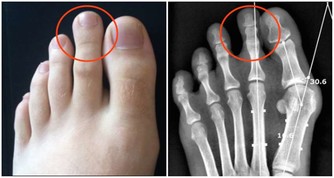

線索四:步幅小

預警:膝蓋骨骼退化

腳後跟接觸地面的一剎那,膝蓋應該保持筆直。如果不是這樣,則意味著可能是膝蓋骨的移動能力或臀部的伸展能力受限,這種功能退化可通過按摩推拿來解決。